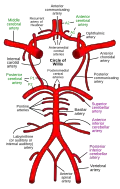

Внутренняя сонная артерия может получать кровоток от важного коллатерального кольца мозговых артерий, более известного как виллизиев круг.

Диаграмма артериальной циркуляции основания головного мозга.

Диаграмма артериальной циркуляции основания головного мозга. Намёт мозжечка. Вид сверху.